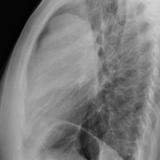

Case 9 Thymoma Lat

Date: 04/04/2010